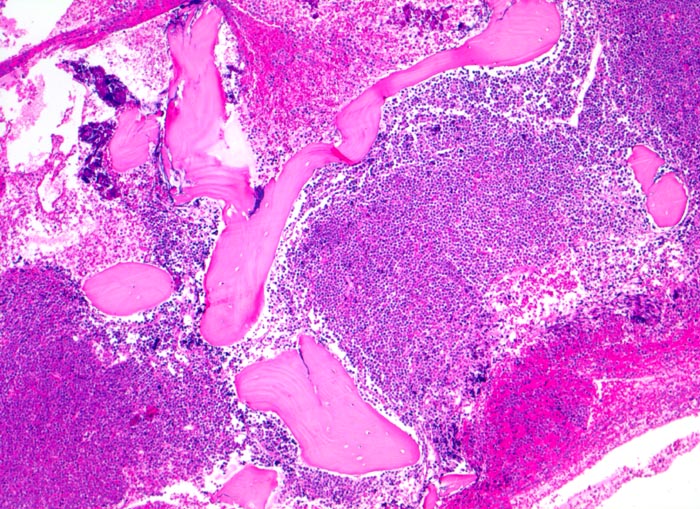

Akute lymphatische Leukämie (ALL)

Knochenmark, Beckenkamm

Verdrängung des Fettmarkes durch diffuse Tumorzellrasen ohne Zerstörung der Knochenbälkchen.

Vergrösserte Lymphknoten, Hepato-Splenomegalie. Knochen- und Gelenkschmerzen, vermehrte Müdigkeit.

Histologie

50